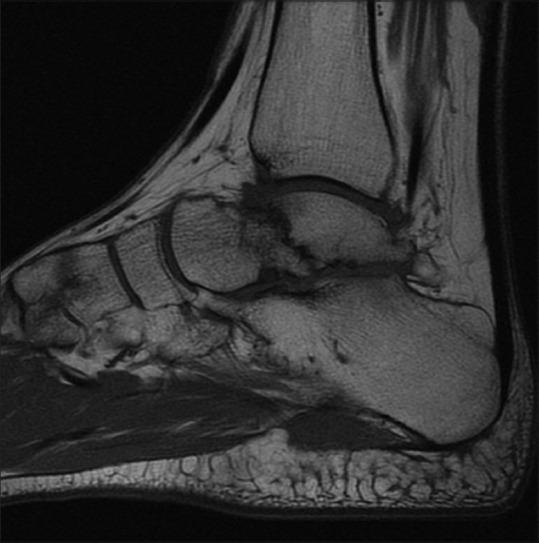

Six patients with talar malunions or nonunions who underwent surgical treatment were reviewed in this retrospective study. There were three nonunions and two malunions of the talar body and one malunion of the talar neck. Clinical evaluation included all the parameters used in the American Orthopaedic Foot and Ankle Society (AOFAS) hindfoot scale. Arthritic degeneration of the ankle joint was assessed according to a modified Bargon scale.

The mean followup was 86 months (range 24-282 months). There were no cases of postoperative avascular necrosis of the talus. Four of the six patients in our series required a subtalar fusion as part of the reconstruction procedure. The average preoperative AOFAS hindfoot score was 34, and at the time of the last evaluation, it was 74. The mean preoperative score on the modified Bargon scale for the tibiotalar joint was 1.17. At the last followup, it rose to 1.33. Three different deformities of the talus were identified (a) flattening of the talus (b) extra-articular step and (c) intraarticular step.

平均随访86个月(范围24 - 282个月)。无距骨术后缺血性坏死病例。我们系列中的6例患者中有4例在重建手术中需要进行距下关节融合。术前AOFAS后足平均评分为34分,在最后一次评估时为74分。改良巴尔贡量表中胫距关节术前平均评分为1.17分。在最后一次随访时,升至1.33分。确定了距骨的三种不同畸形:(a)距骨扁平;(b)关节外台阶;(c)关节内台阶。